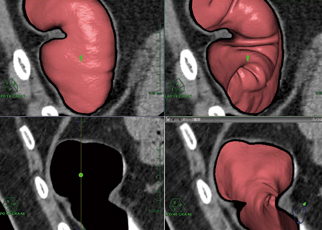

大腸CT解析ソフトウェアでは,仰臥位,腹臥位の画像約2000枚を読み込むと,自動的にクレンジング処理まで行われ,大腸と経路が抽出される(図3)。解析は,“基本解析”“詳細読影”“直交カット断面”“閲覧”“開き一覧”“竹割り一覧”“比較表示”などの機能を使用して行う。クレンジング処理画像とオリジナル画像の切り替えは,ワンクリックで行える。仮想内視鏡画面は,正面からmm単位でカットできるため,大腸断面の表示が可能で,ポリープの観察に適している。

図3 自動でのクレンジング処理後の経路描出 経路は全自動で抽出される。

図3 自動でのクレンジング処理後の経路描出

経路は全自動で抽出される。